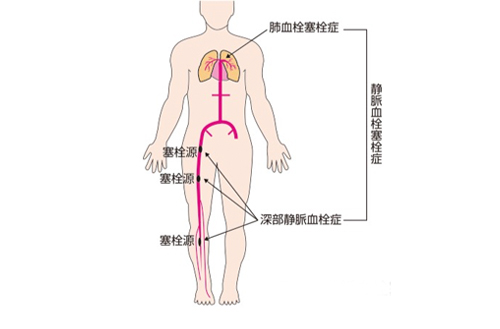

深部静脈血栓症イラスト - No: 24599005無料イラスト・フリー素材なら「イラストAC」。

深部静脈血栓症イラスト無料イラスト・フリー素材なら「イラストAC」。

静脈血栓塞栓症イラスト無料イラスト・フリー素材なら「イラストAC」。

上皇后さまが発症された深部静脈血栓症について解説します下肢静脈瘤の原因・症状・治療方法・予防方法などを専門医が解説。

静脈血栓塞栓症ではどのような症状がありますか? 静脈血栓塞栓症。